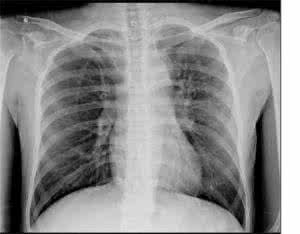

肺癌是一种治疗难度较大的疾病,一般而言随着病情的不断发展加重,肺癌会出现骨转移,有不少患者都在咨询肺癌骨转移死前症状是什么,下面小编就这一问题给大家做一下介绍。

一般到了肺癌晚期,治愈的希望是不大的,只能靠治疗来延长患者的生命,肺癌晚期的症状会出现哪些?不管是骨转移还是淋巴转移,都会有以下症状: